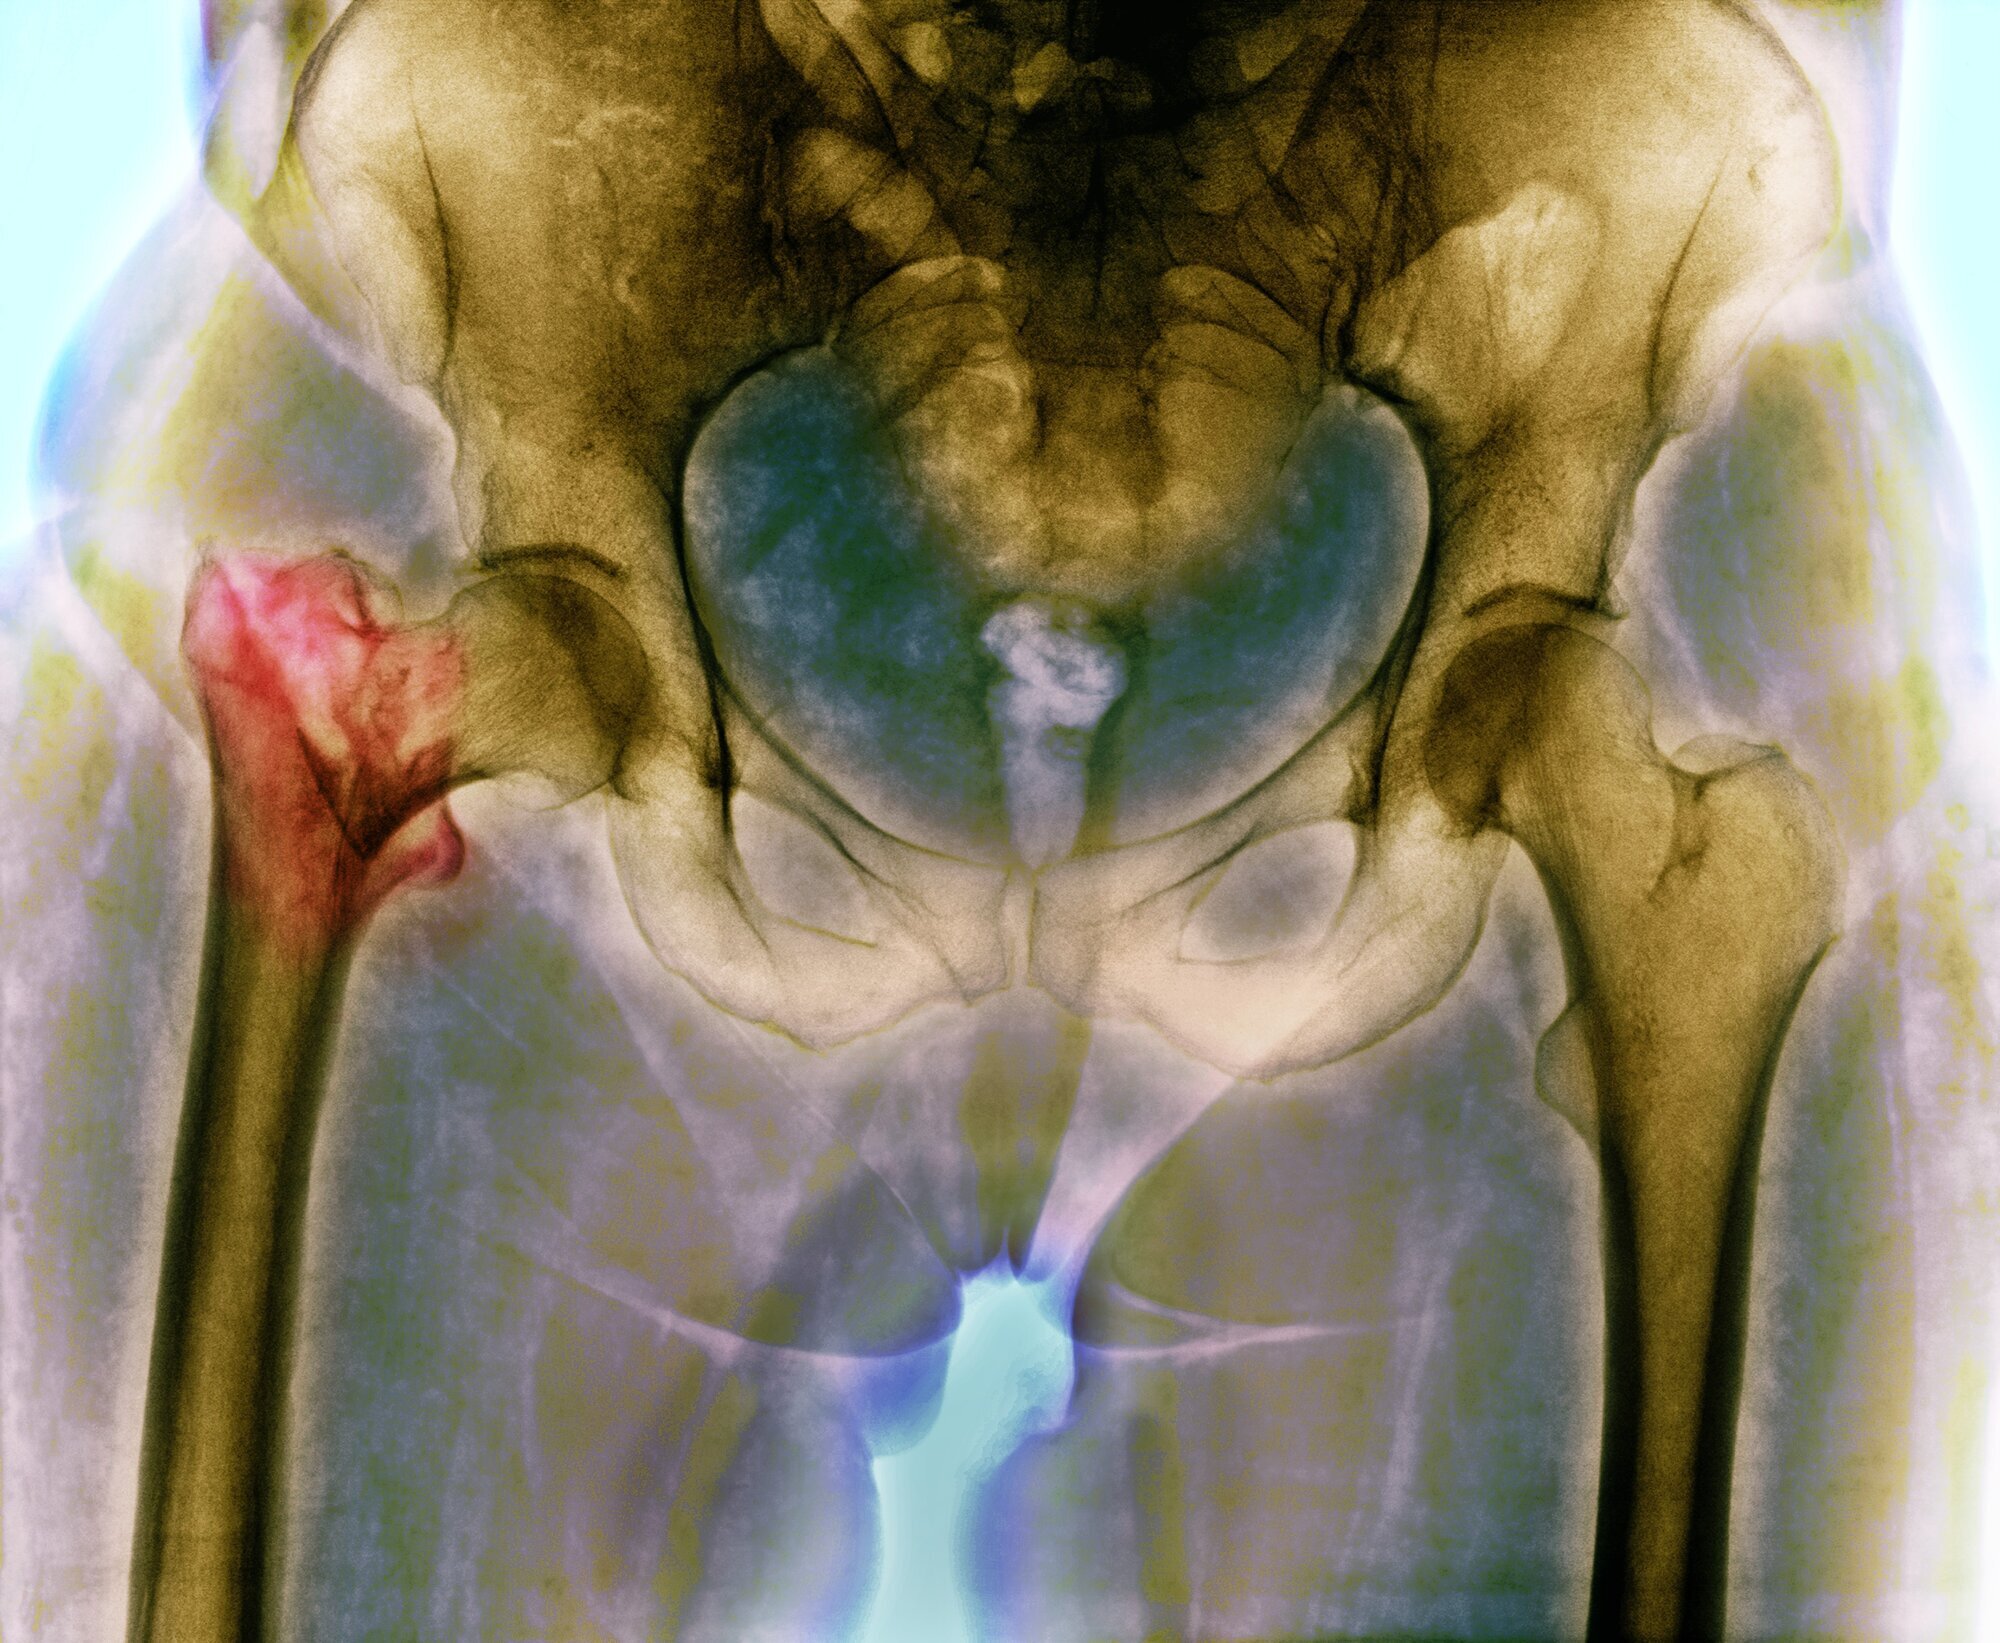

Regjeringen mislyktes i å redusere antall hoftebrudd

Norge har nemlig lenge vært i verdenstoppen på antall hoftebrudd i forhold til befolkningens størrelse.

Fortsatt i verdenstoppen på hoftebrudd

– Selv om vi har hatt en tydelig nedgang i andelen som får hoftebrudd de siste årene, så er Norge fortsatt i verdenstoppen på forekomst av hoftebrudd. Det er flere årsaker til det, mener Jan-Erik Gjertsen og peker på osteoporose (beinskjørhet) som den viktigste faktoren. Norge er også i verdenstoppen på osteoporose.